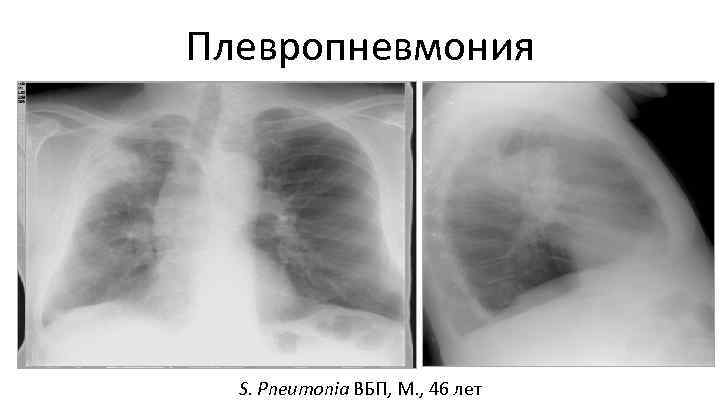

Плевропневмония S. Pneumonia ВБП, М. , 46 лет